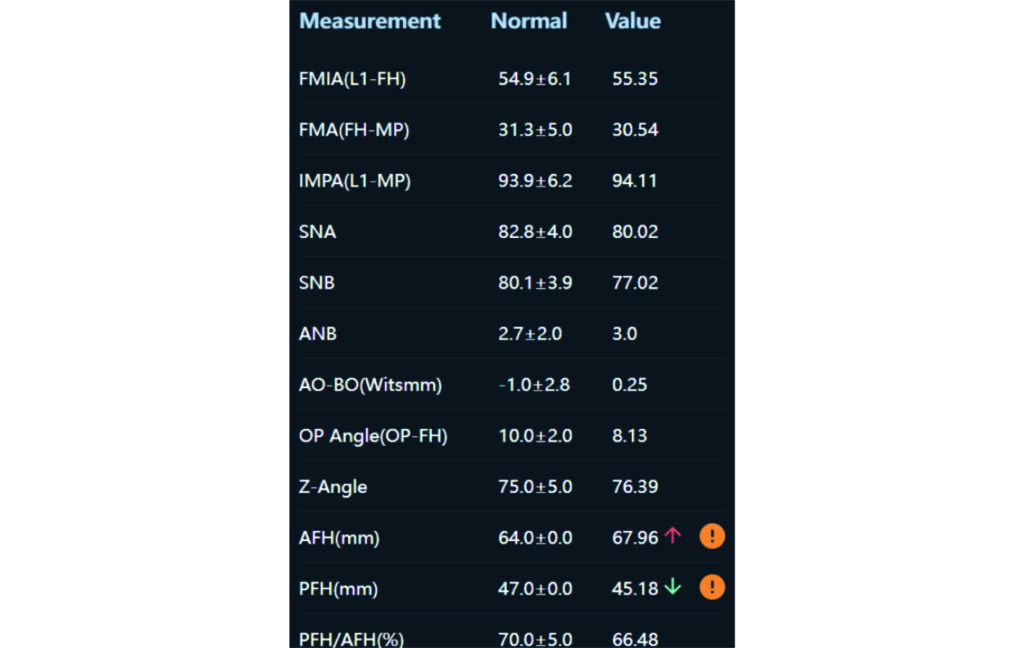

Angle Class II 2mm on the right, Angle Class II 2mm on the left, light mandibular asymmetry to the right, lower central line 1mm to the right, upper central line 1,5mm to the left, 1mm overjet and overbite. Sagittal asymmetry of upper dental arch. Light crowding upper and lower frontal segments, severe attrition of posterior teeth, night bruxism. Normal sagittal position of both jaws, high angle case, steep mandibular ramus,excessive lower facial height, open bite tendency.

Soft Tissue Analysis: convex profile, lower third of the face increased, slightly retrusive upper and lower lips, lip strain on closure.

The case initially presented as a moderate Class II on the right and a Class II tendency on the left, with tapered dental arches and an anterior open bite extending to tooth 26 in segment II.

In segment I, the open bite reached up to the first premolar.

A 1.5 mm deviation of the upper dental midline to the patient’s left was noted, along with a slight mandibular midline shift to the right, likely due to asymmetrical mandibular growth observed in the facial structure. Severe mesial rotations of teeth 16 and 26 were evident in the initial records. As derotation of 16, 26, 17, and 27 progressed up to aligner 16, the premolars in segments I and II moved distally, resulting in a bilateral Class I relationship, as intended in the initial treatment plan.